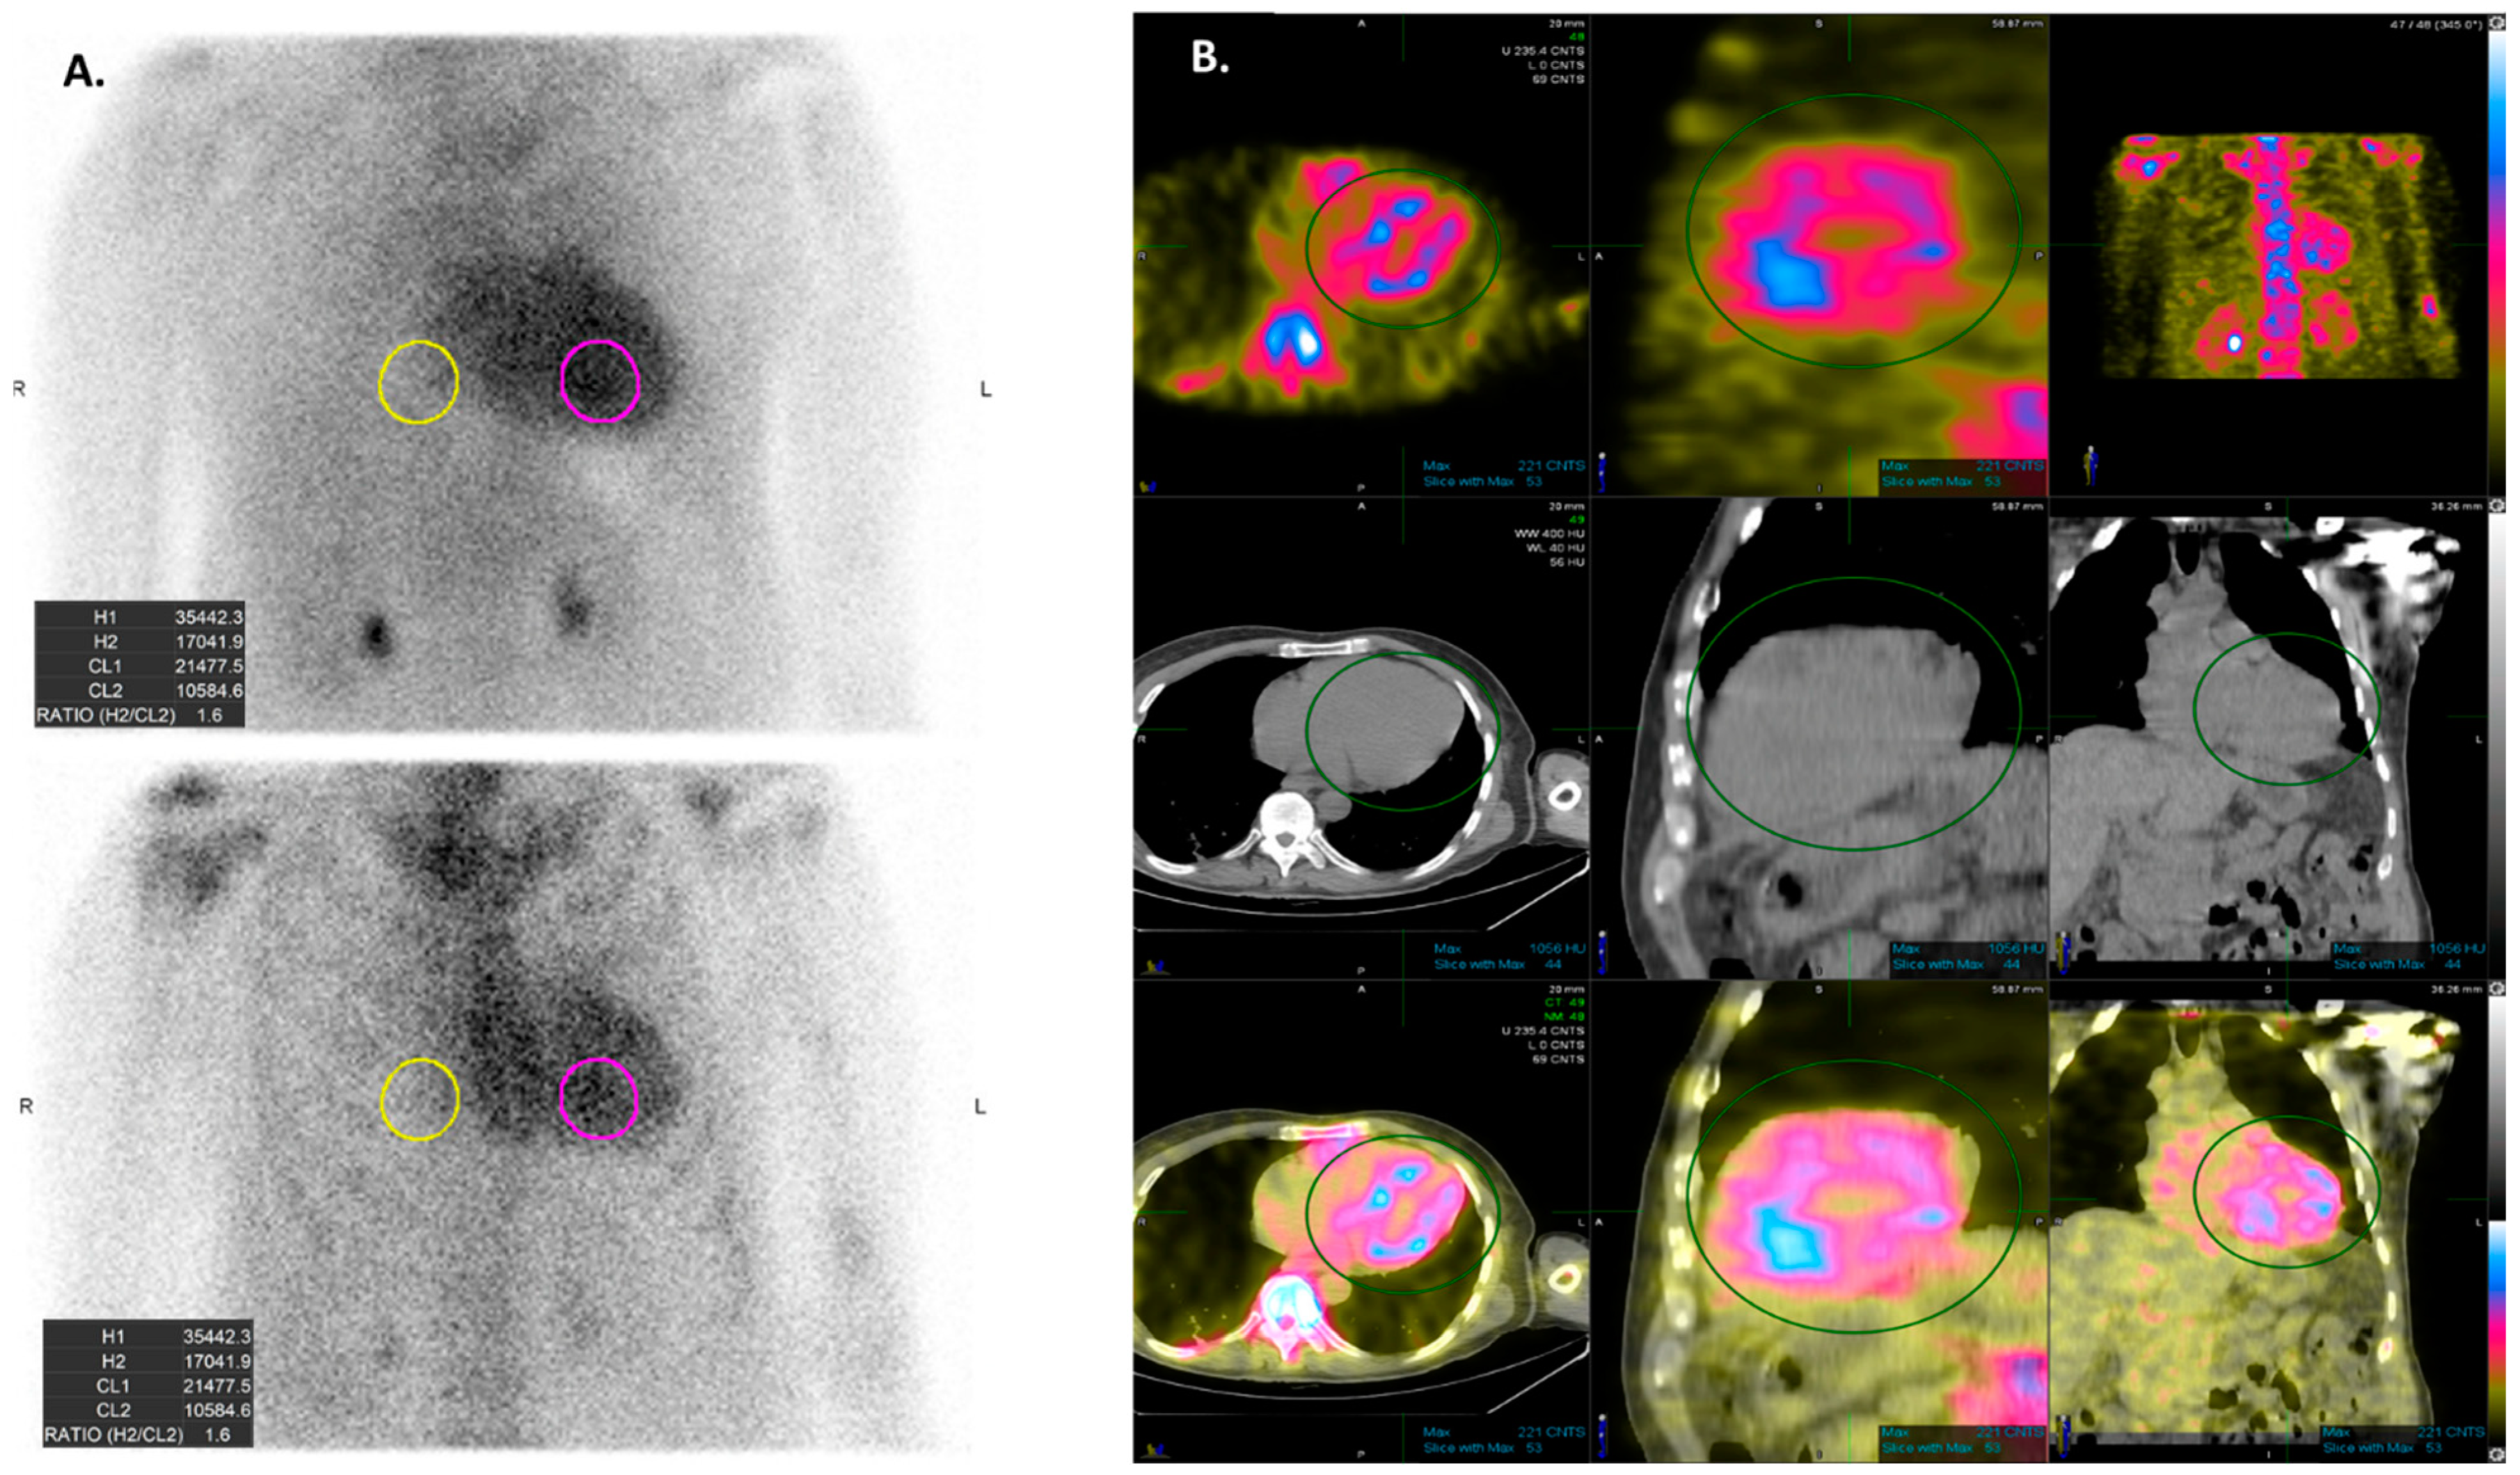

Radionuclide scintigraphy plays a pivotal role in CA diagnosis and determining the appropriate next steps for evaluation. It uses different bone tracers including: 99m technetium (Tc)-labeled 3,3-diphosphono-1,2-propanodicarboxylic acid (DPD), 99mTc-labeled pyrophosphate (PYP), and 99mTc-labeled hydroxymethylene diphosphonate (HMDP) [61]. Quantification of radiotracer uptake intensity is essential and is interpreted using semiquantitative visual analysis.

Although a complete evaluation including a clonal analysis of free light chain immunofixation is warranted to differentiate between ATTR-CA and AL-CA, scintigraphy may help differentiate between the subtypes of CA, as the avidity of bone tracers for transthyretin is much higher than that of immunoglobulin light chains (Figure 4) [62]. The explanation for this finding is still under debate, but it may partially be attributed to microcalcifications in cardiac tissue which were found to be more common in ATTR-CA patients [63,64].

The intensity of radiotracer uptake is classified into three grades according to the Perugini staging system (Table 1) [65]. Grade 2 or 3 positive cardiac scintigraphy without any evidence of monoclonal protein has high sensitivity and specificity for ATTR-CA and may establish the diagnosis without histological confirmation [66,67,68]. However, when monoclonal protein is present, the specificity of the test for differentiating amyloidosis subtypes is markedly decreased [69]. Moreover, the specificity of the test is also low in case of Grade < 2 radiotracer uptake, as AL-CA patients may demonstrate low-grade radiotracer uptake [70].

Figure 4. Technetium-labeled cardiac scintigraphy (PYP scan) is commonly used for the diagnosis of cardiac amyloidosis, especially for transthyretin cardiac amyloidosis. (A) depicts planar imaging with the use of a semiquantitative evaluation using the heart to contralateral ratio. (B) shows SPECT imaging, which allows visualization of the difference in the radiotracer uptake between the left-ventricular blood and the myocardium.